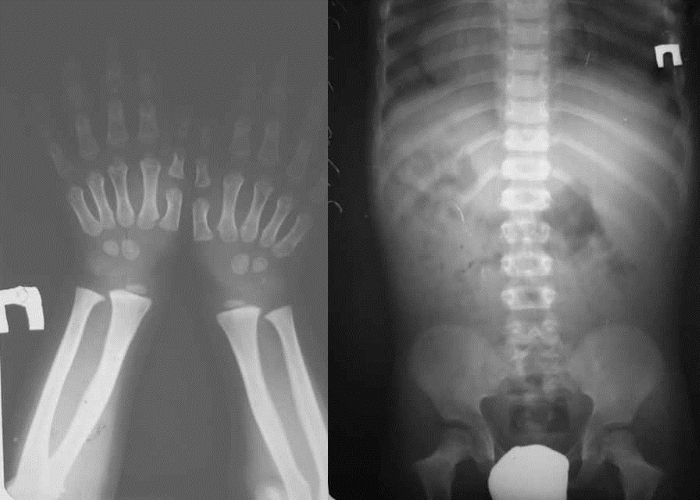

Анализ данных и установление диагноза выполняются педиатром и ортопедом на основании рентгенологического обследования, а также генетических и молекулярных исследований.

Все выявленные нарушения фиксируются при внешнем осмотре и подтверждаются рентгенографией костных структур. На снимках можно заметить сужение спинномозгового канала в области позвоночника и вогнутость контуров задней поверхности поясничных позвонков.

Рентген позволяет оценить уплотнение костей в области плеч и бедер ребенка, небольшое удлинение большой берцовой кости, а также выявить уплощение вертлюжной впадины. В процессе диагностики могут быть обнаружены:

- укорочение локтевой кости;

- наличие квадратных эпифизов в области коленного сустава.